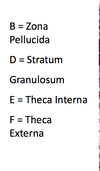

developing antral follicle

antral follicle

graffian follicle ready to ovulate